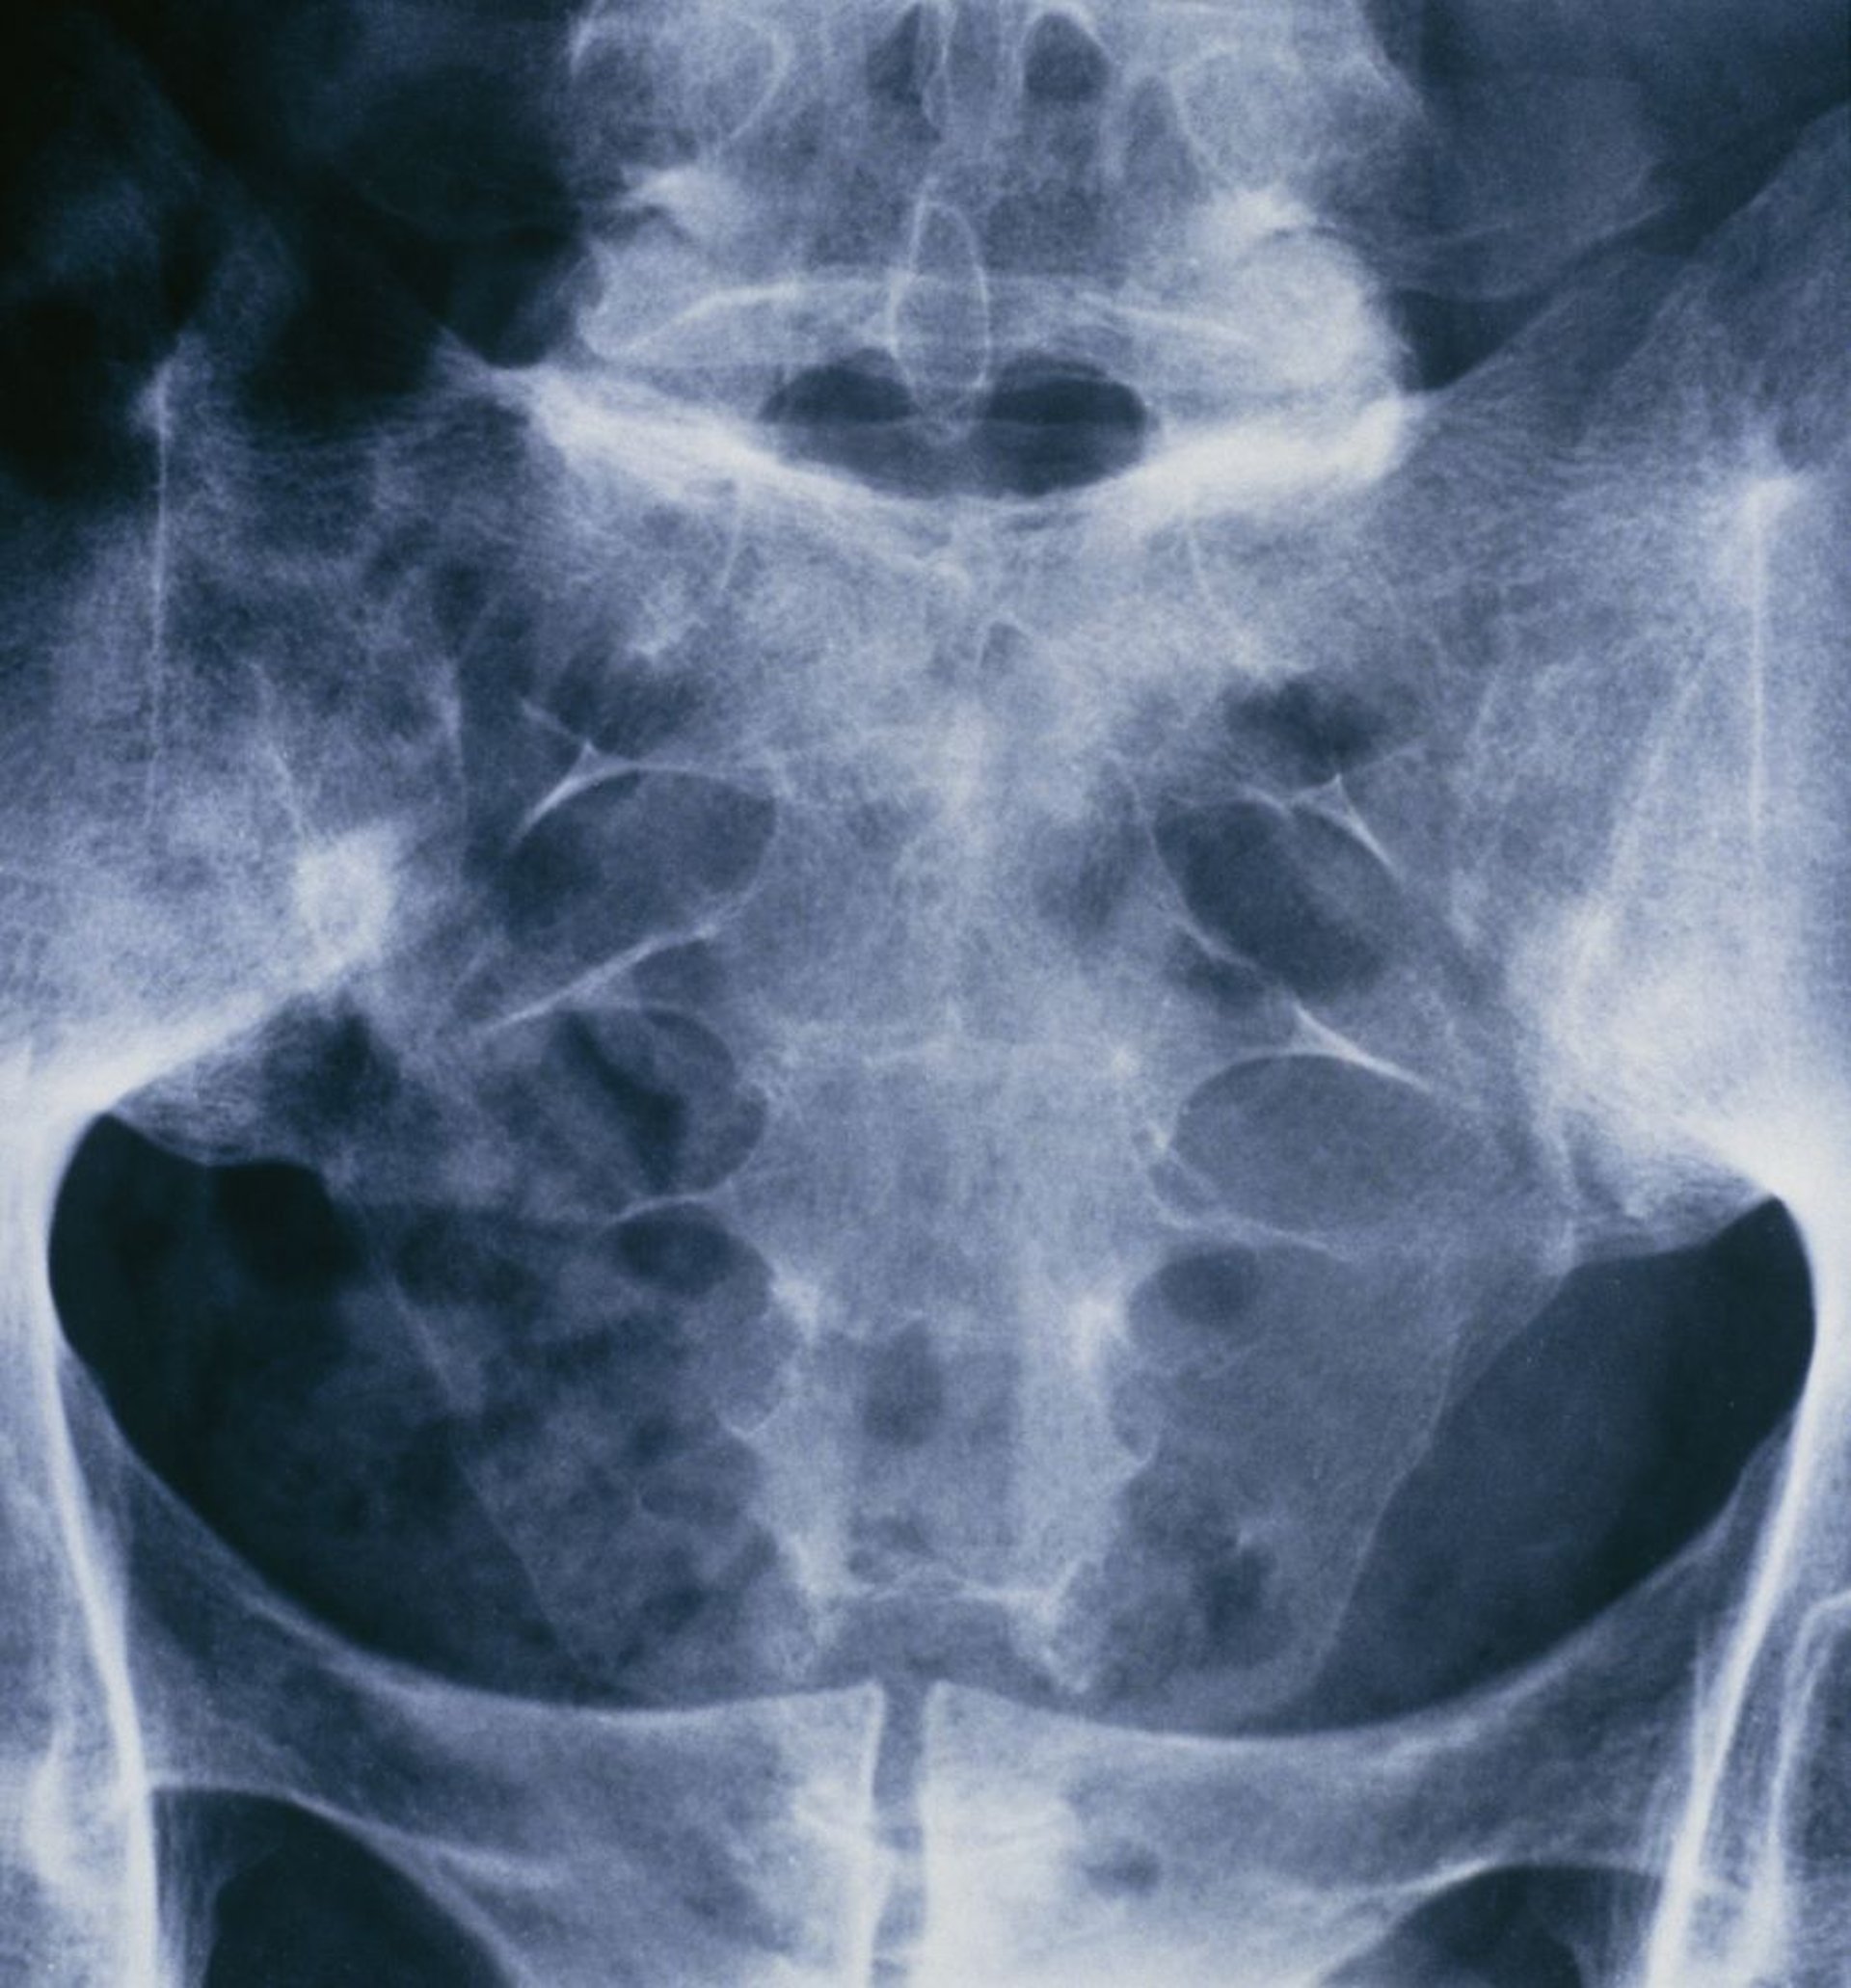

Espondilitis anquilosante (sacroiliitis)

Esta radiografía de la pelvis y la columna vertebral sacra de una persona que padece espondilitis anquilosante muestra la fusión de ambas articulaciones sacroilíacas.

ST. BARTHOLOMEW'S HOSPITAL, LONDON/SCIENCE PHOTO LIBRARY